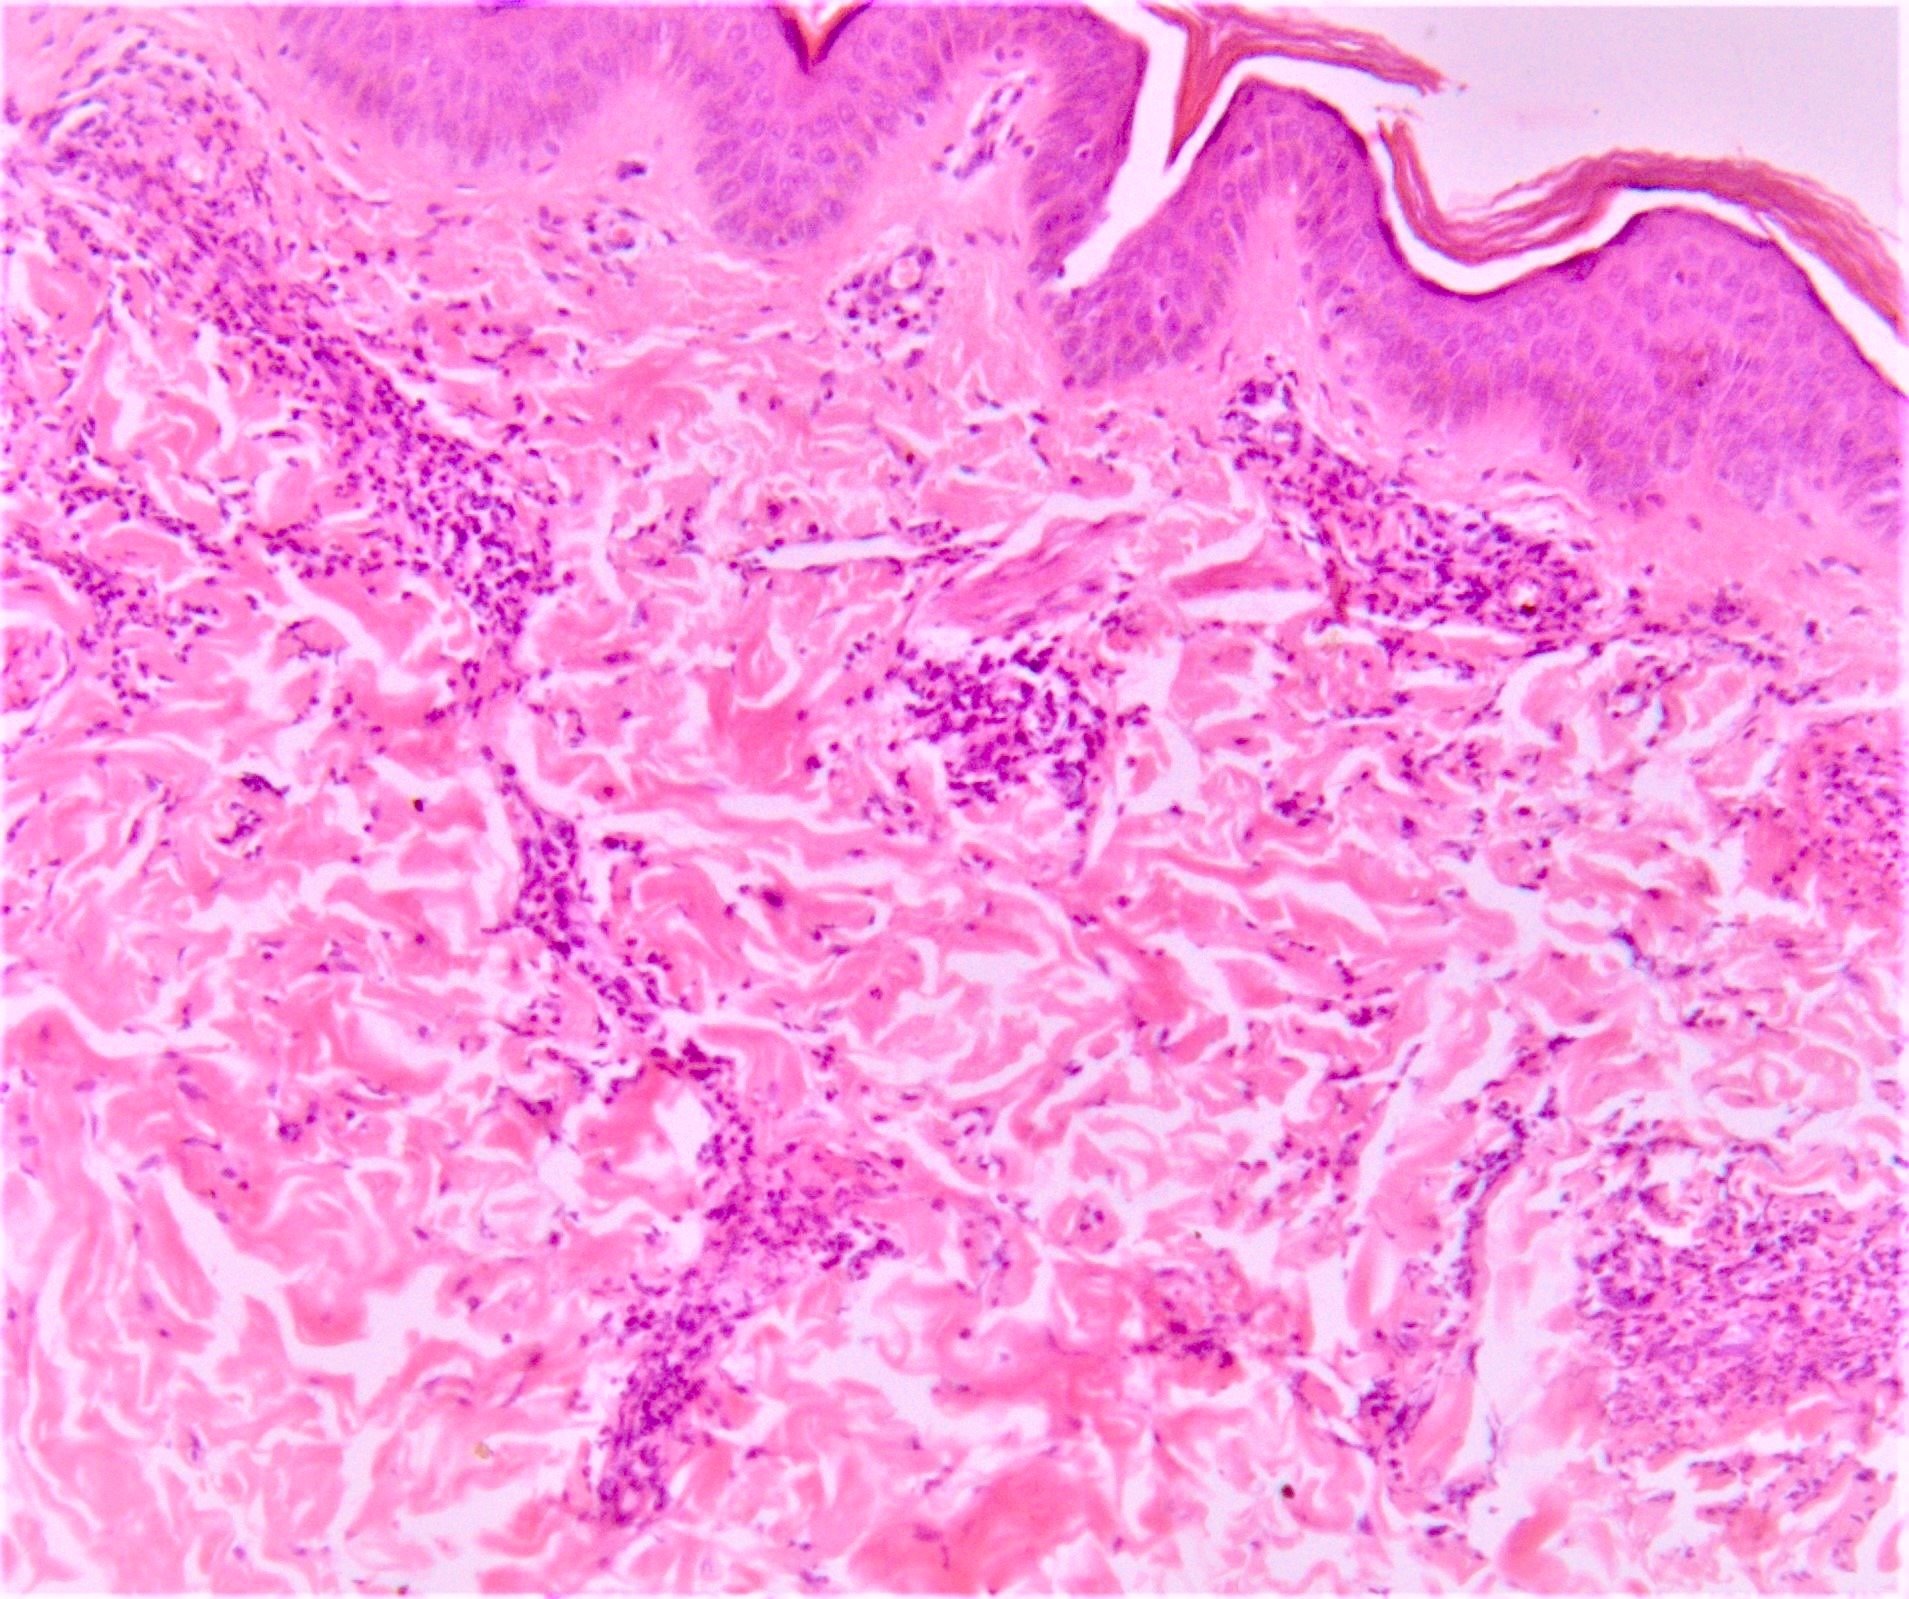

Microscopic (histologic) description

- Erythema nodosum-like lesions: septal panniculitis; vasculitis (lymphocytic or neutrophilic) and necrobiosis may be found

- Reference: Patholog Res Int 2012;2012:209316

Microscopic (histologic) images

- Right leg, erythematous subcutaneous nodule, incisional biopsy:

- Erythema nodosum-like lesion (given the history, compatible with Behçet disease) (see comment)

- Comment: Septal panniculitis with unremarkable epidermis. Dermis shows moderate perivascular lymphocytic infiltrate. The subcutaneous fat demonstrates widening of the fibrous septa with edema and infiltration of lymphocytes and histiocytes. Spillover of infiltrate to the adjacent fat lobules is present. Small focus of lymphocytic vasculitis is noted.